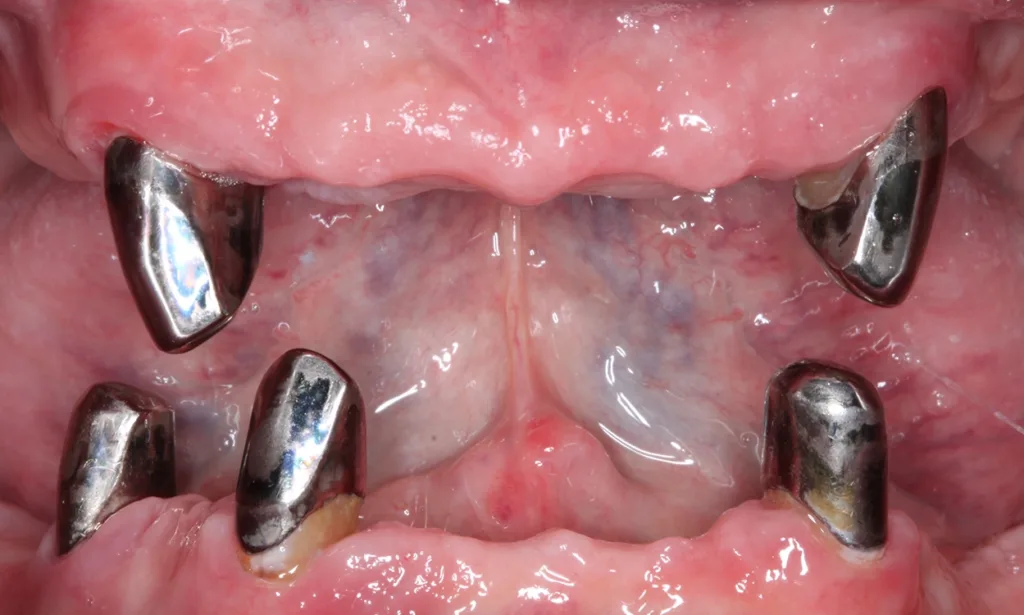

Abb. 3 a–e: Klinische Dokumentation eines 63-jahrigen männlichen Patienten (geb. 05.09.1961). Die Fotodokumentation erfolgte erst am Tag der AIT und nicht im Rahmen der klinischen und radiologischen und 47 wurden vor der AIT entfernt. An den Zahnen 13 und 23 war neben der peniblen subgingivalen Instrumentierung die Applikation von Straumann® Emdogain® (Straumann Group, Basel, Schweiz) vorgesehen.Walter

Abb. 3 a–e: Klinische Dokumentation eines 63-jahrigen männlichen Patienten (geb. 05.09.1961). Die Fotodokumentation erfolgte erst am Tag der AIT und nicht im Rahmen der klinischen und radiologischen und 47 wurden vor der AIT entfernt. An den Zahnen 13 und 23 war neben der peniblen subgingivalen Instrumentierung die Applikation von Straumann® Emdogain® (Straumann Group, Basel, Schweiz) vorgesehen.

Es handelt sich hierbei um einen 63-jährigen männlichen Patienten (geb. 05.09.1961). Allgemeinmedizinisch war eine rheumatoide Erkrankung und die Einnahme von Methotrexat (Folsäureantagonist, Zytostatikum und Immunsuppressivum) dokumentiert. Etwaige orale Nebenwirkungen dieser Medikation lagen nicht vor. Herr B. war Nichtraucher. Der Patient wünschte maximalen Zahnerhalt und wurde daher zur parodontalen Therapie der bereits weit fortgeschrittenen Parodontitis an eine spezialisierte Praxis überwiesen. Zu diesem Zeitpunkt waren im Oberkiefer noch 2 und im Unterkiefer noch 5 Zähne vorhanden.

Der parodontale Screening-Index (PSI) an den verbliebenen Zähnen zeigte erhöhte Zahnlockerungen, stark entzündete und blutende Areale sowie Sondierungstiefen weit über 5 mm hinaus. Es lag dem zufolge ein Code 4* und damit die Notwendigkeit gründlicher Diagnostik vor. Die weiterführenden parodontalen Untersuchungen führten zur Diagnose einer generalisierten Parodontitis Stadium IV Grad C [46]. Die parodontal entzündete Wundfläche betrug 1088,69 mm2 [47]. Radiologisch konnten neben dem generalisierten horizontalen Knochenverlust auch ausgeprägte vertikale Defekte z.B. an den Zähnen 13 und 23 detektiert werden. Darüber hinaus wurde ein Chairside Vitamin-D-Test durchgeführt (Botiss, Straumann Group, Basel, Schweiz). Der Wert betrug 10 ng/ml und bedeutete, dass hier ein schwerer Vitamin-D-Mangel mit entsprechenden Implikationen für den Knochenstoffwechsel vorlag. Dem Patienten wurde eine Vitamin-D-Supplementierung mit zunächst 2000 IE und die Vorstellung bei seinem Hausarzt zu etwaiger weiterer Diagnostik und Festlegung einer optimierten Vitamin-D-Nahrungsergänzung empfohlen [48].

Der Patient wurde über die Krankheitsentstehung, die Prognosen der Einzelzähne und die therapeutischen Optionen aufgeklärt. Es wurde eine systematische parodontale Therapie unter Berücksichtigung der aktuellen EFP/ DGParo-Leitlinien geplant [48]. Der radiologisch sichtbare Knochenverlust an den Zähnen 37 und 47 ging bereits weit über den Apex hinaus. Eine parodontale Therapie erschien daher nicht mehr erfolgversprechend. Die Zähne wurden vor der antiinfektiösen Therapie (AIT) extrahiert und die Alveolen mit adaptierenden Nähten stabilisiert. Im Rahmen der Unterweisungen für eine optimierte häusliche Mundhygiene wurde dem Patienten die Benutzung einer Monobüschelbürste demonstriert und empfohlen. Bei regelmäßiger Anwendung an den vereinzelten, mit Primärteleskopen versorgten Zähnen lassen sich auch diese Zähne in ihrer gesamten Zirkumferenz sehr gut reinigen. Bei den verbliebenen 5 Zähnen war geplant, die zur Verfügung stehenden nichtchirurgischen Möglichkeiten auszuschöpfen. Eine adjuvante Gabe von systemischen Antibiotika war allerdings nicht vorgesehen. Das bedeutete aber, dass im Oberkiefer an den besonders schwer vorgeschädigten Zähnen 13 und 23 neben der subgingivalen Instrumentierung mit Ultraschall und Pulverwasserstrahl (EMS, Nyon, Schweiz) zusätzlich SMP (Straumann® Emdogain®, Basel, Schweiz) appliziert werden sollten [50]. Da beide Zähne einen erhöhten Lockerungsgrad aufwiesen, bestünde die Notwendigkeit einer präoperativen Schienung spätestens vor einer möglichen chirurgischen Stufe-3-Therapie.

Der Punkt, dass beide Zähne demzufolge wohl eher nicht unter optimalen Bedingungen parodontalchirurgisch operiert werden können, hat daher auch zu der Entscheidung einer SMP/EMD-Anwendung in der AIT beigetragen. Die AIT wurde an einem Termin durchgeführt. Nach der Applikation einer Lokalanästhesie wurden alle Zähne zunächst mit Ultraschall und nach Detektion glatter und harter Wurzeloberflächen mit einem erythritolhaltigen Pulverwasserstrahlgemisch mit dem Standard-Handstück behandelt (EMS, Nyon, Schweiz). An den Zähnen 13 und 23 wurden in derselben Sitzung noch zusätzlich SMP – entsprechend einem von Prof. A. Kašaj publiziertem Protokoll (Abb. 5) – appliziert. Zuvor wurde eine Blutstillung unter Verwendung von H2O2 und dem Einbringen von sterilisiertem Superfloss vorgenommen und ein EDTA-Gel zur Konditionierung der Wurzeloberfläche appliziert. Das Aufbringen von Histoacryl® (B. Braun, Tuttlingen, Deutschland) Gewebekleber zum Verschluss der instrumentierten parodontalen „Taschen“ rundete diesen Behandlungszyklus ab. Das detaillierte Vorgehen bei diesem Patienten ist in den Abbildungen 4a–j dargestellt. Da die Zähne nicht geschient werden konnten, wurde der Patient instruiert, auf ein Herausnehmen und Wiedereinsetzen der Prothese sofern möglich in den nächsten Tagen zu verzichten. Nach der AIT wurde die supragingivale Plaquekontrolle an 3 Terminen kontrolliert und die Wundheilung durch professionelle Zahnreinigungen unterstützt.